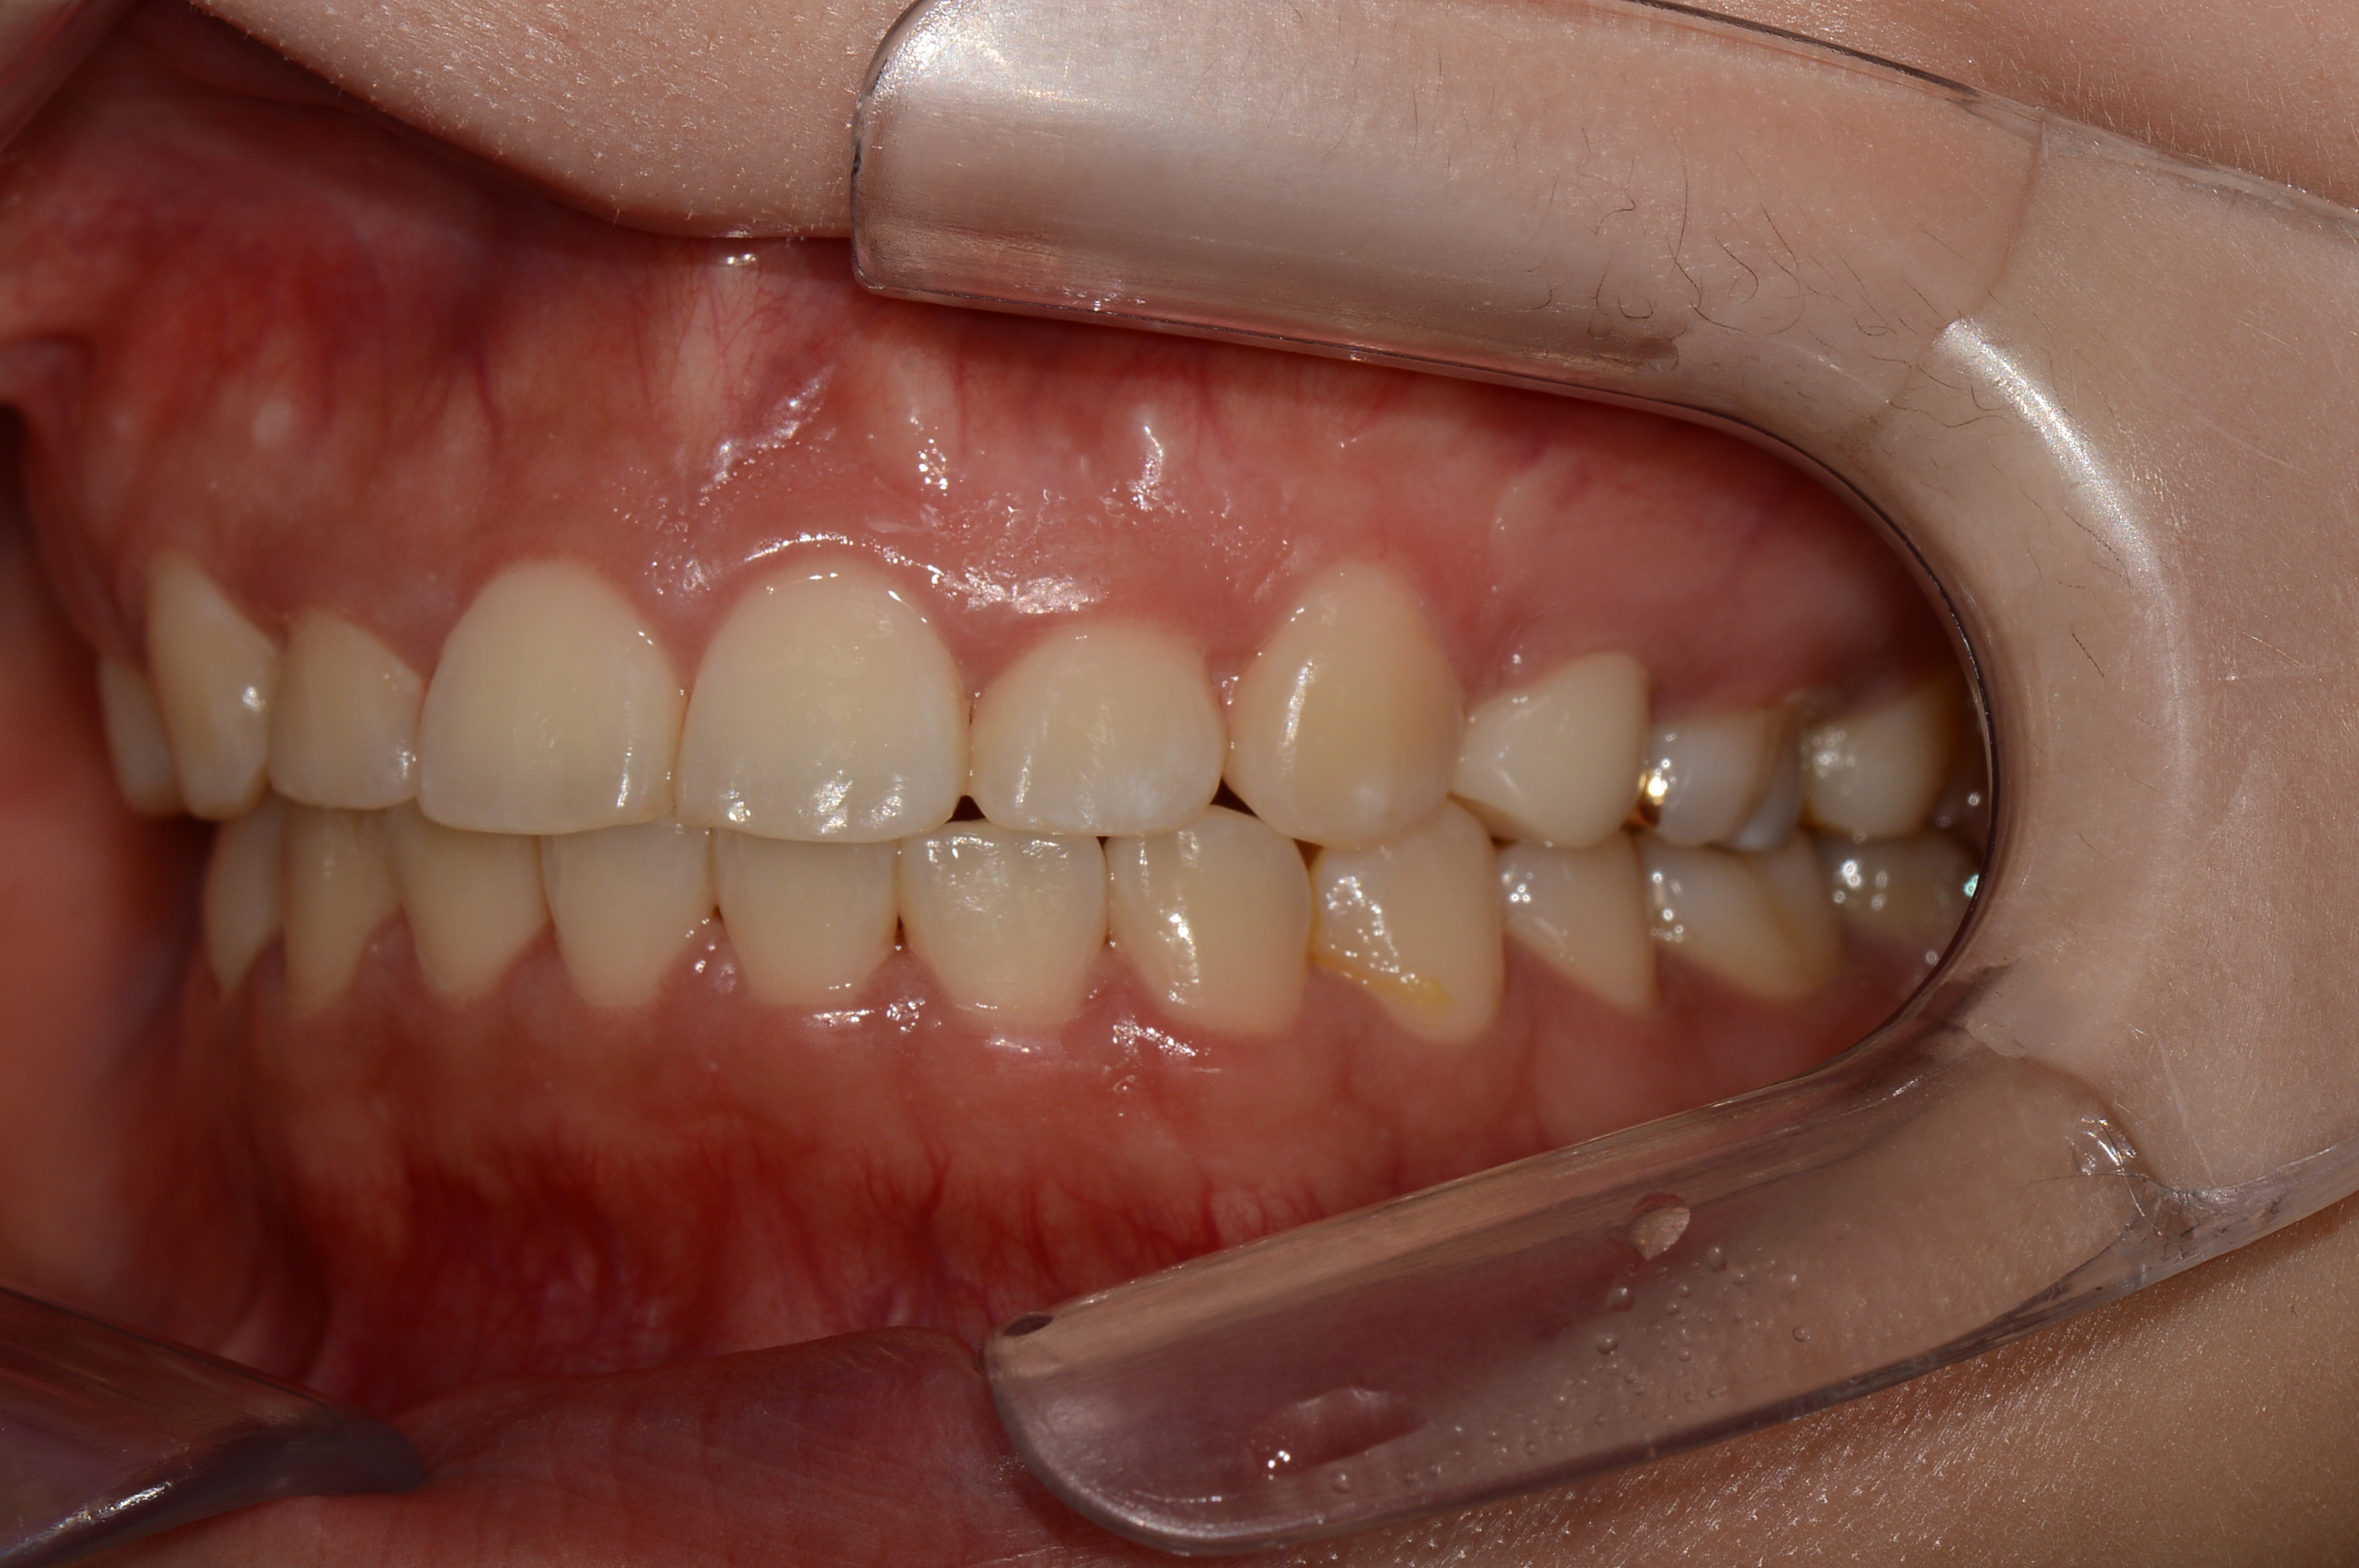

치료 후 사진입니다.